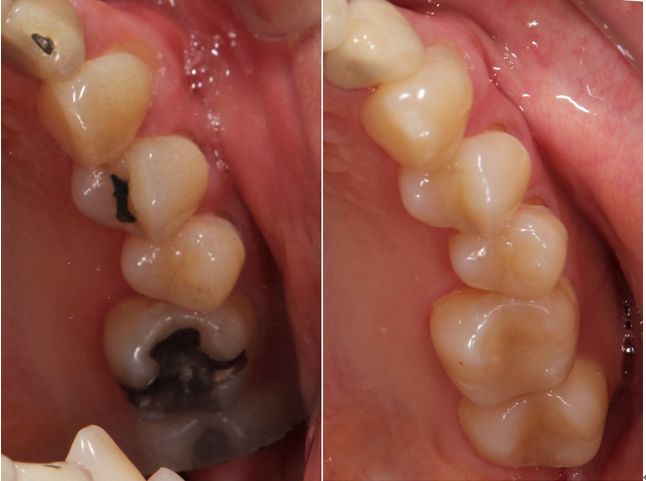

術前術後です。矢印の部分がオールセラミックインレーです。

セラミックインレー

費用11万円

リスクとして歯を削る量が多いため痛みが出る可能性と強い力によって割れる可能性がある。